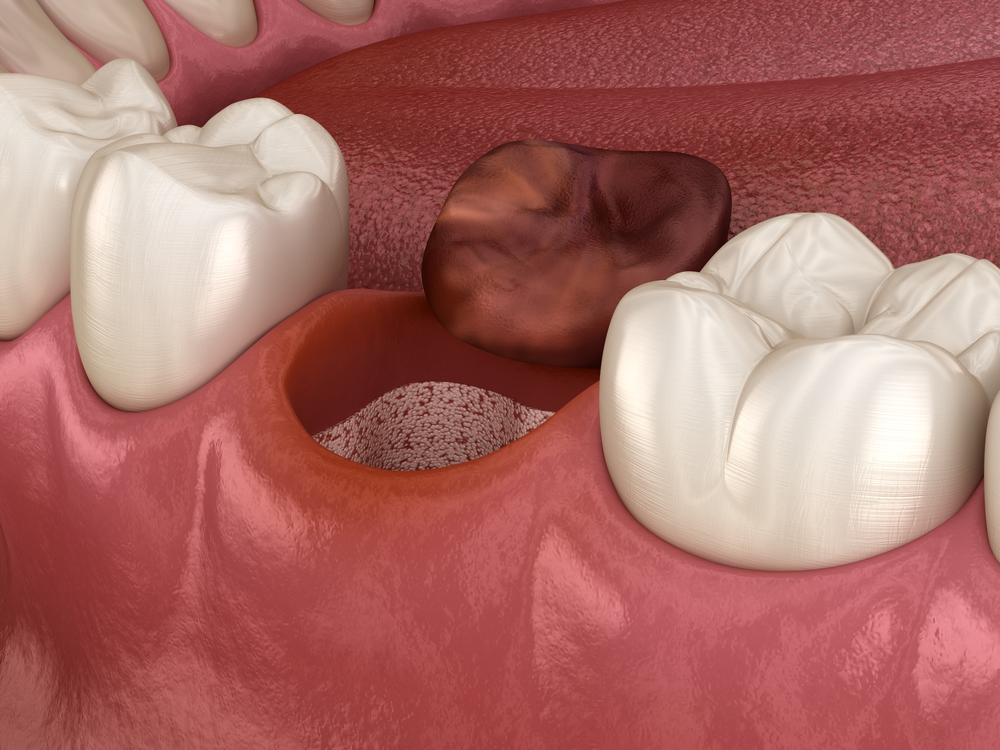

What is Post-Tooth Extraction Inflammation (Alveolitis)?

What is Post-Tooth Extraction Inflammation (Alveolitis)? 7 August 2025 Blog What is Post-Tooth Extraction Inflammation (Alveolitis)? Post-tooth extraction inflammation, medically known as alveolitis , occurs when the expected blood clot at the extraction site either fails to form or dislodges prematurely. During normal healing, a blood clot forms in the space where the extracted tooth was located. […]